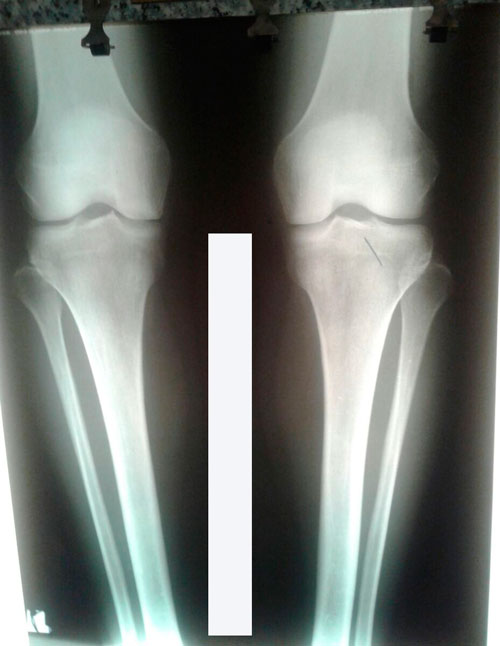

Исходник - 42 года.

Дата операции - 18.01.2017г.

РЕНТГЕН ДО ОПЕРАЦИИ